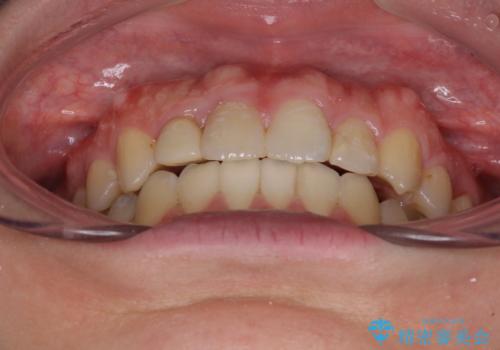

上下の骨幅を改善したことで、スムーズに歯列矯正を行うことができました。

奥歯の咬み合わせを改善する必要があったため、治療は長期化しましたが、きっちりと仕上げることができました。